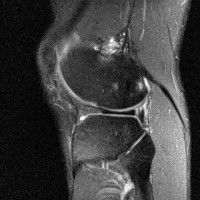

무릎 mri 간단히 봐주실 수 있으시나요 ㅠㅠ

안녕하세요 8년전 십자인대 수술하고 최근 무리한 운동에 무릎 불편감이 생겨서

mri 찍었습니다.

진단결과는 첫 찍은 병원에서 활액막염 이라는 진단을 받았습니다. 혹시 봐주실 수 있으실까요?

올라온 MRI가 단편적이라서 정확한 진단에 어려움이 있지만 십자인대에는 큰 이상이 있지는 않은것 같으며, 무릎관절내 물이 있는 것으로 보아 활액막염의 진단이 맞을 것 같습니다.

하지만 단편적인 영상이기 때문에 촬영병원에서 정확한 판독지 등을 받으시는 것이 좋겠습니다.